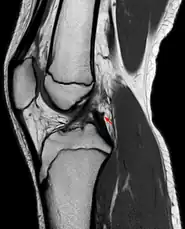

Posterior meniscofemoral ligament on MRI, sagittal

Posterior meniscofemoral ligament (Wrisberg) behind the posterior horn of the lateral meniscus close to its insertion. Sometimes wrongly interpreted as a meniscal tear.